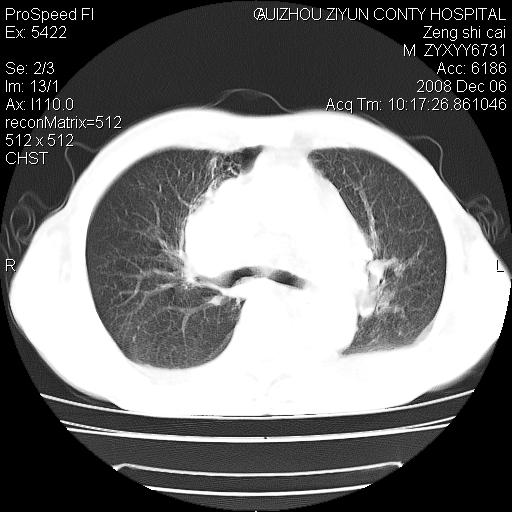

标题: CT16961:M、71岁,咳嗽半年,无血痰;胸片示右肺占位。 [打印本页]

标题: CT16961:M、71岁,咳嗽半年,无血痰;胸片示右肺占位。

右肺癌并纵隔淋巴结及胸膜转移可能性大

右肺癌并纵隔淋巴结及胸膜转移。建议气管镜

右肺纵隔型肺癌伴纵隔淋巴结及胸膜转移!

右肺纵隔型肺癌伴纵隔淋巴结转移!双侧胸水!

1)考虑右肺上叶纵隔型肺癌伴纵隔淋巴结转移。2)心包积液,双侧胸腔积液。

右肺癌并纵隔淋巴转移,腹膜后转移可能性大,两侧胸腔积液

右肺上叶纵隔型肺癌伴纵隔淋巴结转移。心包积液,双侧胸腔积液。

右上肺癌并纵隔淋巴结及胸膜转移。

右肺纵隔型肺癌伴纵隔淋巴结转移!双侧胸水\\心包积液

建议强化!主要鉴别是淋巴瘤与肺癌淋巴结转移。

右肺纵隔型肺癌伴纵隔淋巴结及胸膜转移